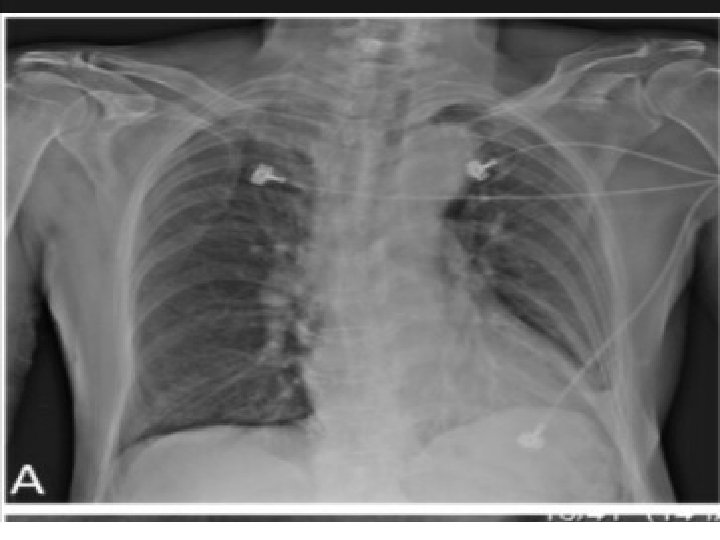

QUESTION 3 • A 69 yr old male with h/o HTN and t 2 DM presented with sudden onset of substernal chest pain and SOB. patient was anxious and diaphoretic in the emergency. vital signs showed a BP reading of 130/90 mm. Hg and HR of 68 bpm. Physical examination was otherwise unremarkable.

ANSWER • Aortic Dissection

QUESTION 4 • A 63 yr old man was brought to emergency dept in cardiac arrest. he had a h/o HTN , DLP, CAD. pt c/o dizziness and dyspnoea prior to his syncope. his initial BP was 70/40 mm. Hg , HR 68 bpm , SPO 2 82% in RA.

------ • CAG Non obstructive epicardial coronary arteries and patent LAD 2 D ECHO Dilated Rt ventricle Rt sided heart catheterisation revealed RV pressure of 80/30 mm. Hg

Pulmonary angiogram disclosed filling defect s/o B/L pulmonary embolism